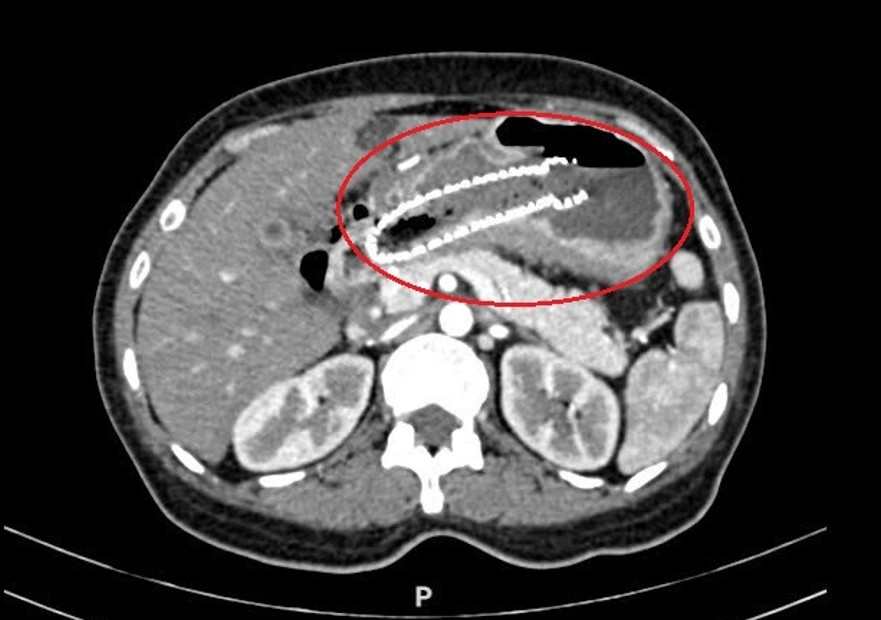

Ảnh chụp CT của chị Quyên cho thấy khối u dạ dày chèn ép tá tràng. (Ảnh: BVCC)